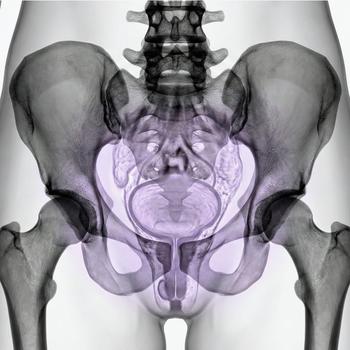

MRI Pelvic – for gynecological problems, cysts or suspected endometriosis

If you have pain in the lower abdomen, irregular bleeding, fertility problems or suspect that something is not right in the lower abdomen, an MRI examination of the pelvis can be the next step to get the right diagnosis. MRI pelvic, also called MRI gynecology, is a painless and radiation-free examination that provides very detailed images of both the uterus, ovaries and fallopian tubes.

The examination is used when other methods such as ultrasound or gynecological examination have not been able to explain your symptoms. With the help of MRI, conditions such as endometriosis, fibroids, cysts, tumors, malformations or effects on nearby organs such as the bladder or intestines can be detected. It is also an important method before fertility treatment or in preparation for surgery.

Whether you are seeking answers to long-term symptoms or following up on previous findings, pelvic MRI gives you and your doctor a clear picture that can form the basis for the right treatment and continued care.